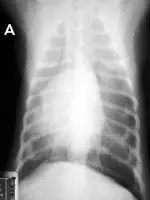

FIGURE 2

Signs of retraction of the lung lobes from the thoracic wall and blunting of the costophrenic angles (A) are best appreciated on the DV view (versus VD view) unless a large amount of air is present. Close-up of the DV view (B) shows air between the thoracic wall (white arrows) and lung (black arrows).